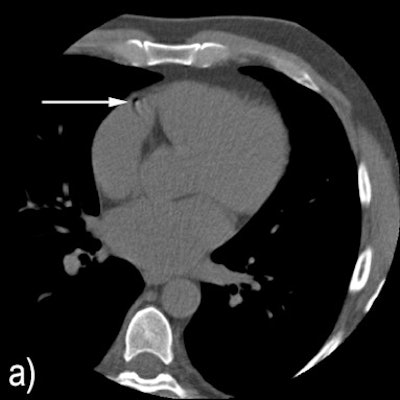

Two examples where the system disagreed with reference annotations. Above) A motion artifact in the RCA that the system detected as a coronary calcification. Below) A coronary calcification in the distal RCA that was not identified by the system. All images courtesy of Dr. Jelmer Wolterink.In addition, ambiguity detection with expert review may enable automated CAC scoring with performance comparable to that of a human expert," added Wolterink and colleagues Dr. Tim Leiner, Dr. Richard Takx, and colleagues from University Medical Center Utrecht in the Netherlands (IEEE Transactions on Medical Imaging, September 2015, Vol. 34:9, pp. 1867-1878).